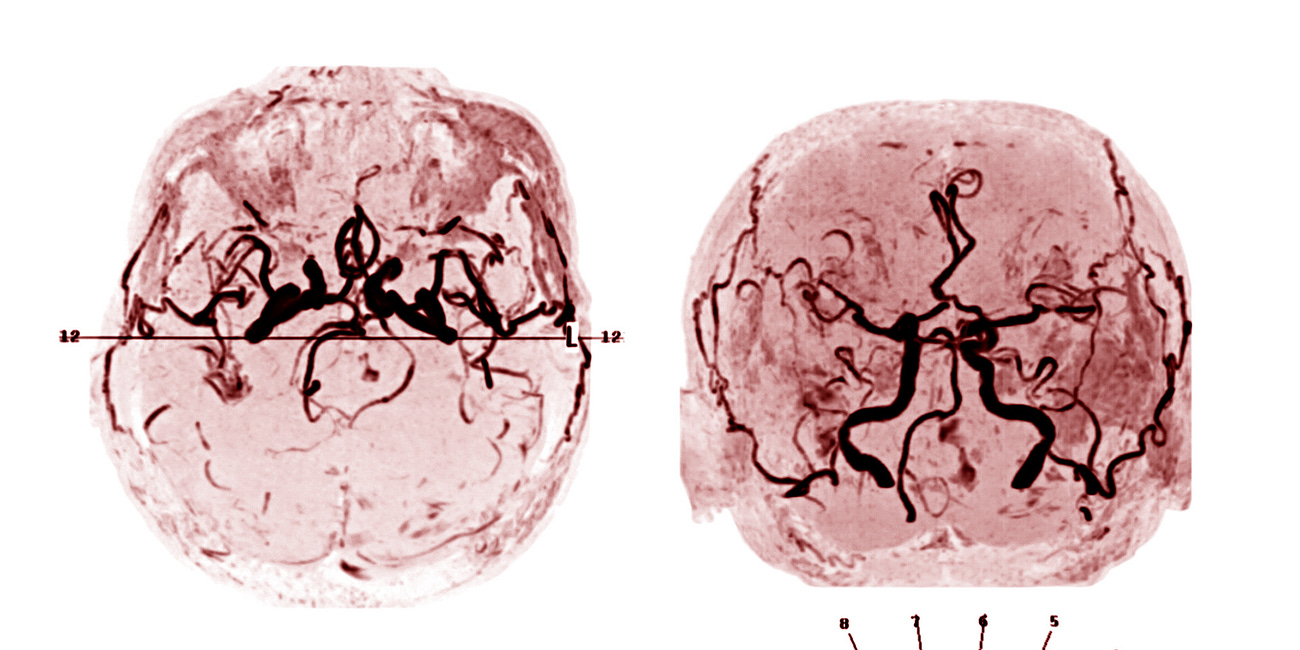

Brain death imaging tests are unreliable (INDex study)

To help make the diagnosis of brain death, specialized brain imaging tests are endorsed in many U.S. hospitals’ policies for patients who cannot complete an apnea test or other key aspects of the exam.